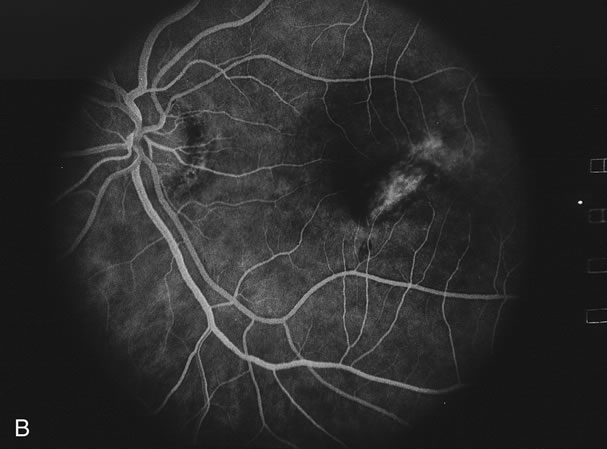

Fig. 11. A. Subretinal fibrosis in a case of multifocal choroiditis. B. Fellow eye showing classic coalescent hyperpigmented chorioretinal scars of multifocal choroiditis. These scars also can be seen in presumed histoplasmosis syndrome, but the subretinal fibrosis is extremely rare in presumed ocular histoplasmosis syndrome (POHS).